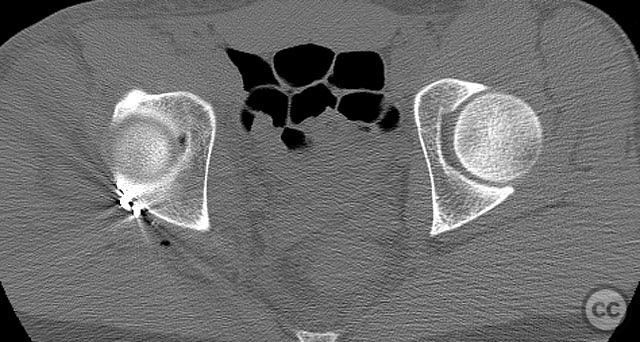

Clinical and radiological findings:  A 20-year-old male collegiate basketball player sustained a displaced right posterior wall (PW) acetabular fracture-dislocation during practice. Initial AP pelvic radiograph demonstrated a reduced femoral head with a displaced posterior wall fragment. Axial CT imaging revealed a large, peripherally located PW fragment with significant displacement, impaction into the abductor muscle mass, and no intra-articular comminution. Obturator oblique radiographs and intraoperative fluoroscopy under anesthesia demonstrated mechanical obstruction to passive abduction at 10–20 degrees due to the relationship between the displaced PW fragment and the greater trochanter.

Intraoperatively, the posterior wall fragment was found firmly embedded within the abductor musculature, necessitating careful disimpaction and minimal periosteal stripping to preserve vascularity. The spring-hook device provided secure capture of the peripheral fragment without involving the labrum. Placement of the reconstruction plate medial to the hook tines provided buttress support to prevent secondary displacement. Fluoroscopic imaging confirmed anatomic reduction and extra-articular screw placement. Postoperative CT demonstrated satisfactory reduction and implant positioning.